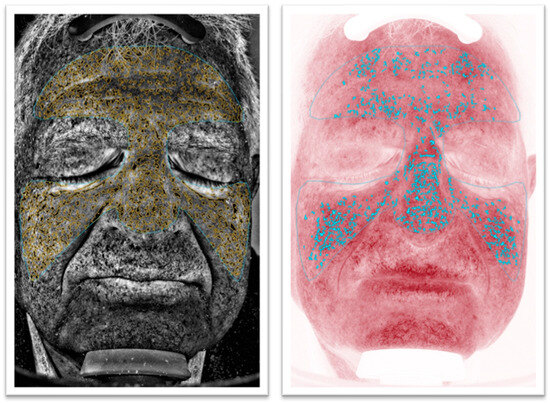

2.2. Imaging Check-Up Procedure

3.1. VISIA® Evaluation